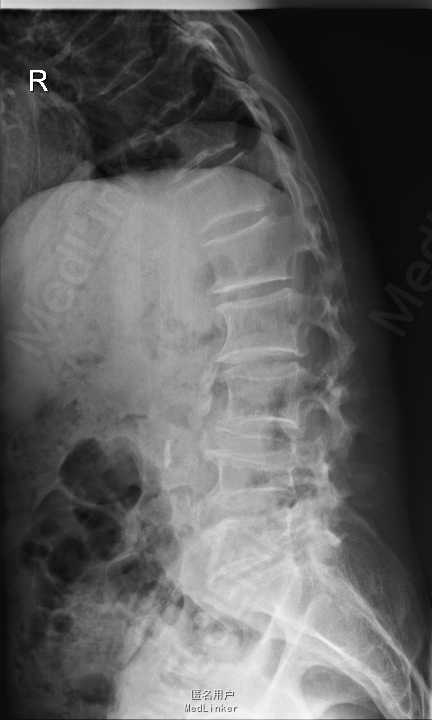

腰痛5年,加重伴左下肢放射性疼痛半个月 患者5年前无明显诱因出现腰痛,不伴下肢放射性疼痛、麻木、无力,腰部活动受限,劳累后加重,平卧休息可缓解。半个月前无明显诱因出现腰痛加重,伴左下肢放射性疼痛、麻木,腰腿活动受限,无低热、盗汗,无纳差、消瘦。

查体:左侧小腿外侧、足背感觉减退,右侧正常,双侧屈髋、伸膝、踝背伸肌肌力5级,左侧踇背伸、跖屈肌肌力4级,右侧踇背伸、跖屈肌肌力4-5级,双侧巴氏征阴性,直腿抬高试验左侧30°阳性,右侧阴性。 辅助检查: X-ray:腰椎退行性变,腰椎节段性性不稳 MR:腰椎间盘突出,腰3/4,4/5,腰4/5节段明显

诊断:腰椎椎管狭窄 处理: 1、完善相关辅助检查,明确诊断,有无手术指证; 2、完善手术评估,有无手术禁忌,手术风险及并发症; 3、在全麻下行腰椎后路减压,腰3/4左侧椎板减压,腰4/5椎间Cage植骨融合内固定术

随访 术后患者下肢麻木感觉较前好转,左侧踝背伸、跖屈肌力4级+,左侧肢体抬高试验阴性。术后MR检查减压彻底 讨论:1、腰椎椎管狭窄手术指证的把握,腰椎后路手术,腰椎椎间融合与椎板减压的选择? 2、术中探查如无明显间盘突出,以椎管骨性狭窄为主,可行腰椎后路椎板减压为主。